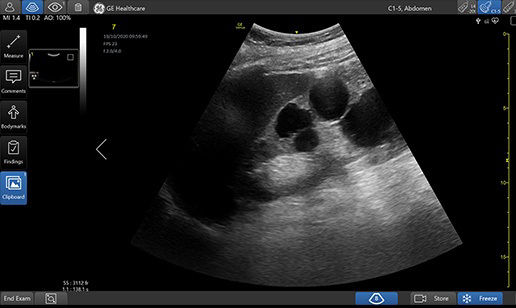

Quickly assess kidneys and the bladder with Renal Diagram

Simplify documentation and provide easy follow up for patients with suspected hydronephrosis. No need to type findings; simply assign a label from a pre-populated list that correlates with images.